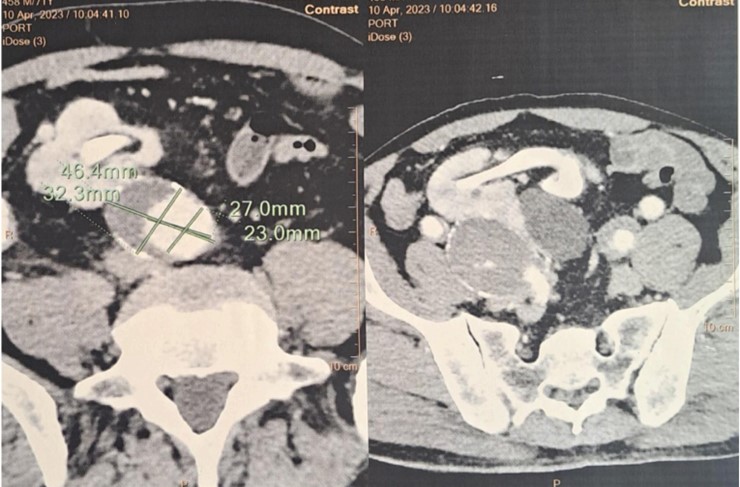

A 73-year-old man with a history of nephrolithiasis presented with abdominal pain. Computed tomography angiography (CTA) demonstrated an 89 mm infrarenal AAA extending to the iliac arteries, with the left iliac artery measuring 32 mm and the right iliac artery 27 mm. An ectopic right pelvic kidney was identified, perfused by the right internal iliac artery. Baseline renal function was preserved, with creatinine clearance at 54.7 ml/min/1.73m².

Figure: Computed tomography angiography (CTA) demonstrated an 89 mm infrarenal AAA extending to the iliac arteries, with the left iliac artery measuring 32 mm and the right iliac artery 27 mm. An ectopic right pelvic kidney was identified, perfused by the right internal iliac artery.